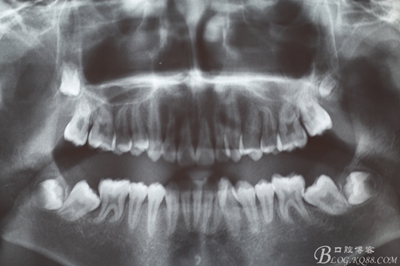

圖1.術(shù)前患者的全景片檢查:38、48牙冠已經(jīng)形成,牙冠方向?yàn)樗轿唬?7、38近中位萌出。